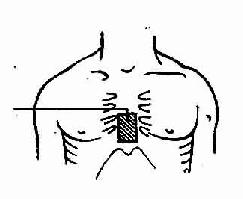

3.按压部位 在胸骨下1/3段。确定部位用以下方法:术者用靠近病人足侧一手的食指和中指,确定近侧肋骨下缘,然后沿肋弓下缘上移至胸骨下切迹,将中指紧靠胸骨切迹(不包括剑突)处,食指紧靠中指。将另一手的掌根(长轴与病人胸骨长轴一致)紧靠前一手的食指置于胸骨上。然后将前一手置于该手背上,两手平行重叠,手指并拢、分开或互握均可,但不得接触胸壁。

胸外心脏按压正确部位